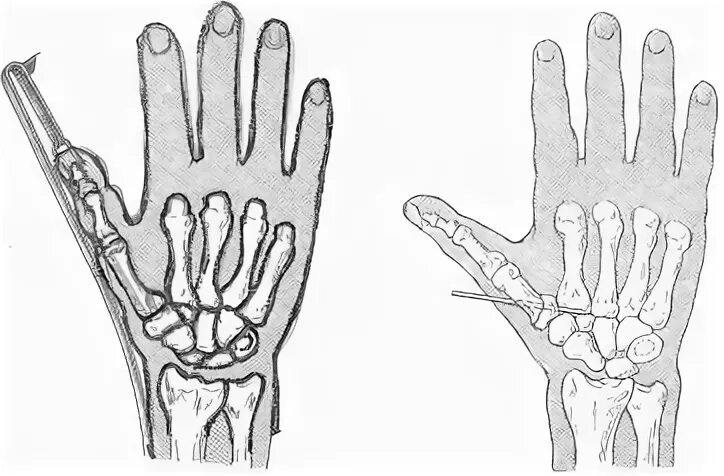

Перелом первой пястной кости перелом беннета. остеосинтез 1 пястной кости. перелом проксимальной фаланги 1 пястной кости. остеосинтез перелома пястных костей кисти.

Остеосинтез спицей перелом пястной кости. остеосинтез 2 пястной кости спицами. остеосинтез пястной кисти. перелом беннета остеосинтез.

Перелом беннета репозиция. репозиция операции костей. операция при переломе беннета. репозиция костей кисти.